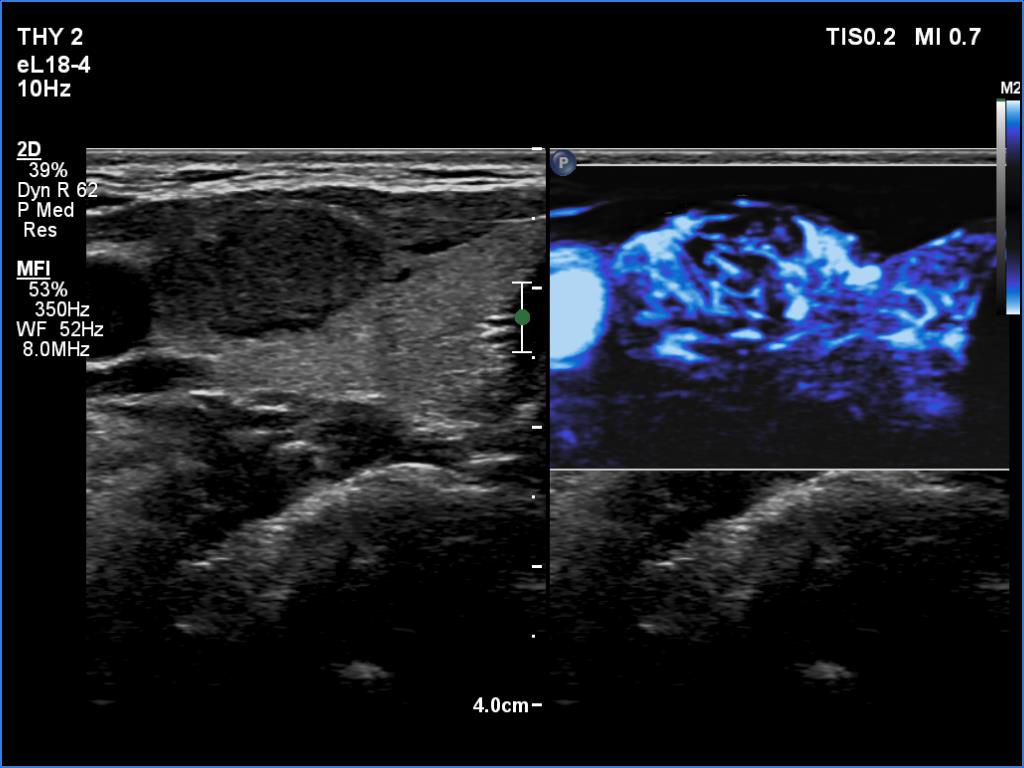

Right lobe, longitudinal scan

Right lobe, transverse scan, microflow imaging. The tumor is rich in vessels.